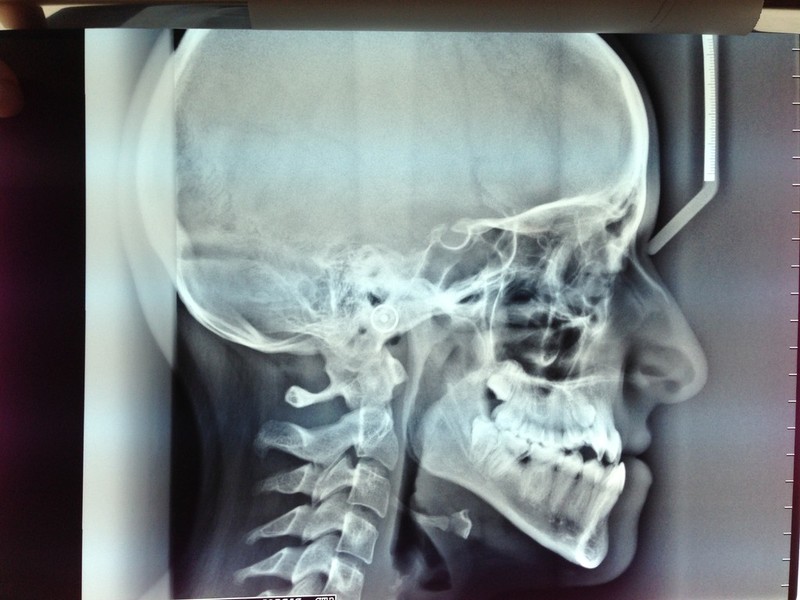

Paziente candidato a intervento di chirurgia Ortognatica